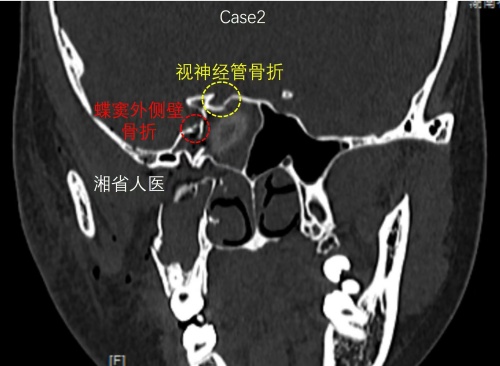

术前CT可见视神经管骨折、蝶窦外侧壁骨折

小艺入院后,医生检查发现其右侧瞳孔已出现散大,对光反射消失,视力已无光感。进一步检查发现,小艺右侧视神经管骨折、颅底多发骨折并颅内积气、蛛网膜下腔出血,右侧颧弓、右侧上颌窦前壁及后外壁、右侧眼眶外侧壁多发骨折。耳鼻咽喉头颈外科三病区周建波主任医师表示,外伤性视神经受损属于急危重症,若不及时对视神经管的骨折片进行清理,解除被压迫的视神经,小艺的右眼将会永远失明。